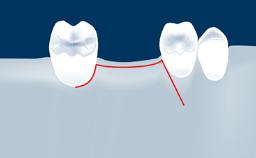

Following tooth loss, alveolar resorption and ongoing pneumatization of the maxillary sinus may lead to vertical and horizontal bone deficits in the posterior maxilla.

This deficit reduces the distance between the maxillary sinus floor and the alveolar process, so that reconstructing the vertical bone height by means of a sinus floor elevation procedure may be a prerequisite for placement of dental implants of the correct dimensions and in the ideal three-dimensional positions in order to achieve optimal functional and esthetic treatment outcomes while respecting relevant anatomical structures.

• list the indications for the lateral SFE technique

• describe the surgical treatment concept and steps for the lateral SFE technique and assess the prognosis of this procedure